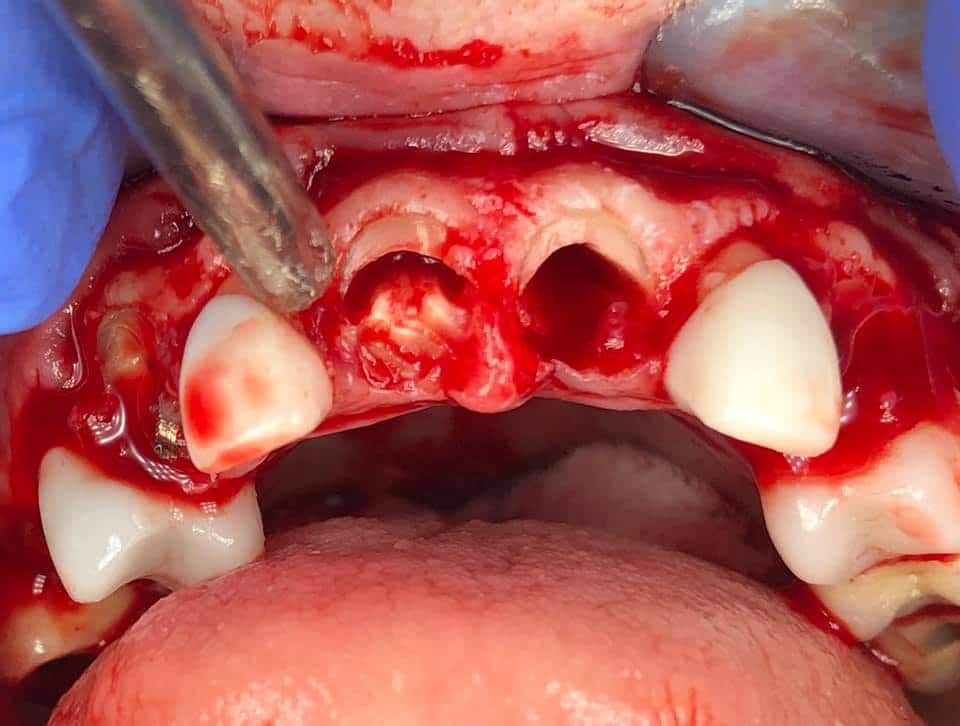

Below is a case of full arch same day temporization using the socket shield , root submergence and pontic shield techniques to preserve the site architecture . Neodent GM implants were placed in a guided fashion and same day temporization was performed using a milled PMMA.